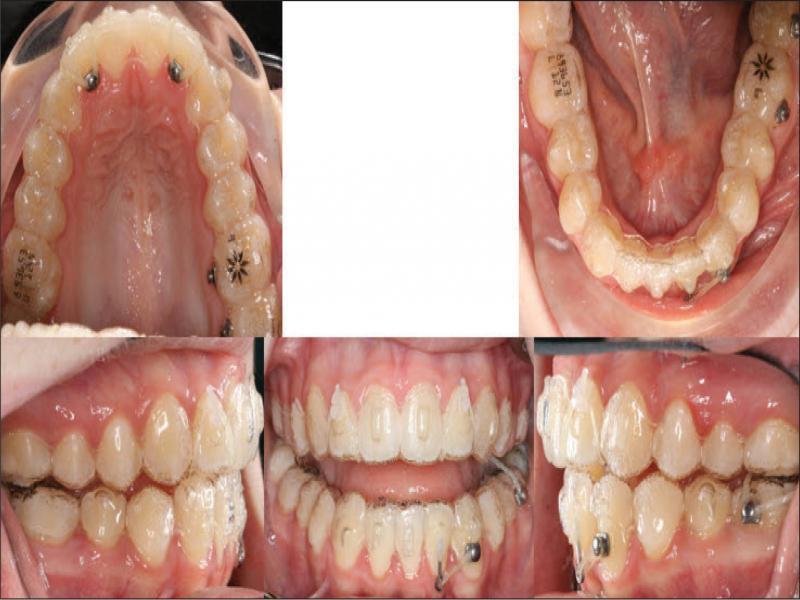

With these considerations, it was planned to treat the patient by the extraction of the lower right central incisor (41), by transverse dental arch expansion, and the management of the vertical relationships by avoiding mechanics that would tend to extrude posterior teeth. The 41 was chosen for extraction as it allowed for alignment of the remaining lower incisors, largely through mesial crown tip. In addition, there was slightly less gingival attachment on 41 and the tooth had a small incisal fracture. The extraction of 31 would perhaps have been more advantageous for the alignment of 32 but would have necessitated a more challenging bodily translation of 41 rather than mainly mesial crown tip. It was considered that clear aligner therapy would be beneficial from a vertical perspective, by minimising the extrusive mechanics inherent to fixed appliances. Figure 4 shows the prescribed finishing position of the dentition. Vertical control was augmented by the placement of occlusal bite pads in the aligners themselves on the occlusal of the molars in both arches to provide a bite-plane effect posteriorly (Figure 5). Furthermore, the absence of fixed appliances serving as a predisposing factor is favourable in managing concerns regarding the patient’s oral hygiene and cariogenic dietary intake.

Invisalign® predicted outcome showing attachments.

Auxiliary treatment was successfully employed to assist poorly tracking tooth movements, rather than submitting the case for additional aligner orders (Figure 11):

Auxiliary treatment during aligner treatment.

The left buccal transverse relationship was corrected by the assistance of posterior cross-elastics (¼” 4.5 oz worn from the buccal of the lower left molars to the palatal of the upper left molars).

Power arm mechanics were used to assist the uprighting of 32. The initial ClinCheck® plan perhaps failed due to poor attachment choice for this tooth. This was rectified on refinement, when a long vertical attachment was placed to assist root uprighting. Nonetheless, even with the appropriate attachment, auxiliaries were required to assist in completing desired root uprighting of this tooth. This demonstrates the occasional incomplete expression of desired tooth movements by aligners (Figure 12).

Both upper lateral incisors had bonded appliances placed labially and lingually for the application of bootstrap elastics (3/16” 3.5 oz) to extrude these teeth into the aligner, after they had intruded unwantedly, despite the presence of appropriate attachments on the teeth.